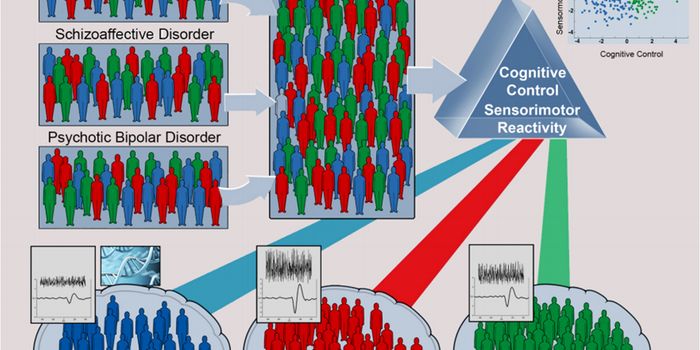

APR 09, 2021NeuroscienceUp to 1 in 4 people are affected by mood disorders in their lifetimes. Due to a lack of objective diagnostic procedures, ...